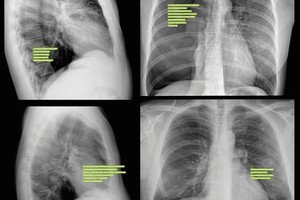

Al día de la fecha se encuentran internadas 552 personas en camas de unidades para adultos Covid-19, lo que representa 19% del disponible en la provincia. Y hay 88 con asistencia respiratoria mecánica, un 15,9% del total.